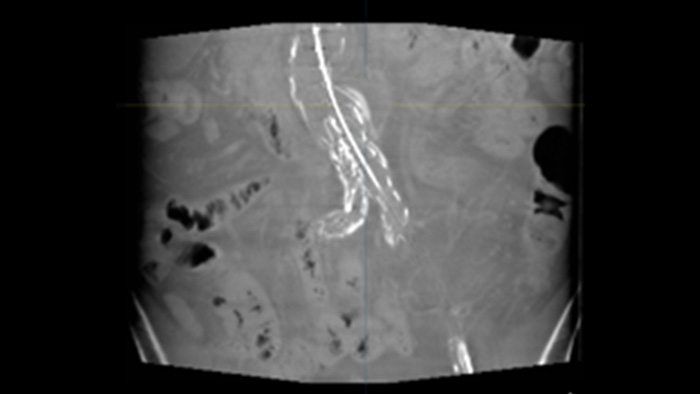

2d perfusion vascular

VesselNavigator allows reuse of 3D vascular anatomical information from existing CTA and MRA datasets as a 3D roadmap overlay on a live X-ray image. With its excellent visualisation, VesselNavigator provides an intuitive and continuous 3D roadmap to guide you through vasculature.